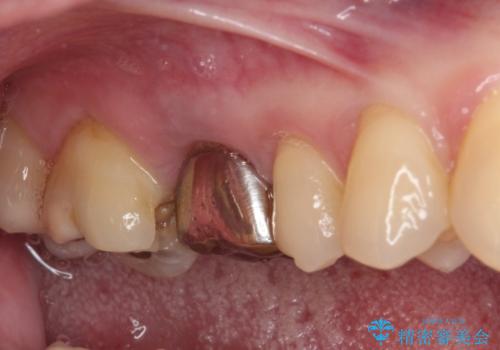

ゴールドインレーは銀歯のインレーやセラミックインレーと比べ、「技工操作の精度が高く、適合が著しく良い」というメリットがあります。特に上の奥歯は歯科医師の操作が行いにくいため、「適合の良さ」は再治療のリスクを防ぐ上でとても重要な要素となります。

上の奥歯は金属色が見えることもないため、審美的な問題は全くありません。

咬み心地はとても良好で、全く違和感がなく、患者様には大変満足していただきました。